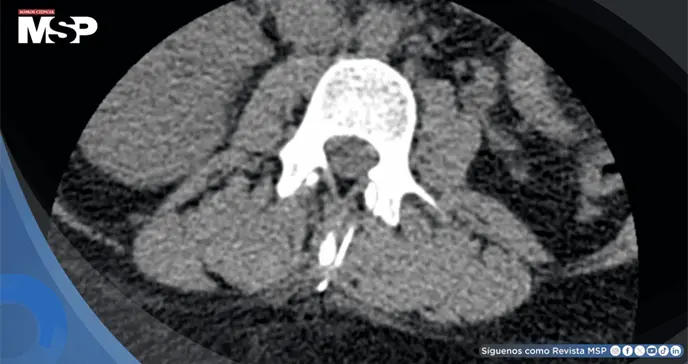

La tomografía computarizada confirmó la presencia del fragmento metálico lineal ubicado en la musculatura paravertebral a nivel L3, aproximadamente 1 cm lateral al proceso espinoso. No se identificó compromiso del canal espinal, hematoma epidural ni otras complicaciones asociadas. La localización superficial del fragmento fue determinante para la planificación terapéutica.